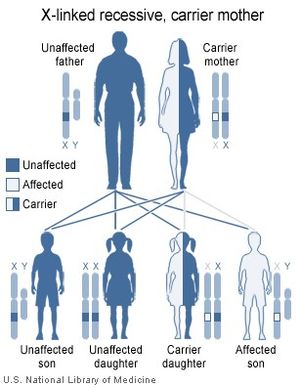

يعتبر عمى الألوان من الأمراض الوراثية حيث تحمله الأم في جيناتها ولا يظهر عليها وتورثه لأبنائها من الذكور أكثر من الإناث.

وعمى الألوان وراثي. فاذا تزوج رجل مصابٌ بعمى الألوان، امرأة لم يكن في تاريخ أسرتها عمى ألوان، فإن رؤية أولادهما للألوان ستكون طبيعية. ومن ناحية أخرى، فإن بناتهما سيحملن جينات عمى الألوان، ويمكن أن ينقلنه إلى أطفالهن. أما إذا تزوجت امرأة وكان والدها مصابًا بعمى الألوان، رجلاً رؤيته طبيعية، فإن أبناءهما تكون لديهم فرصة بنسبة خمسين بالمائة لوراثة هذا الخلل. وتسبب إصابات الشبكية أو العصب البصري، وأمراض عديدة للعين، عمى الألوان.